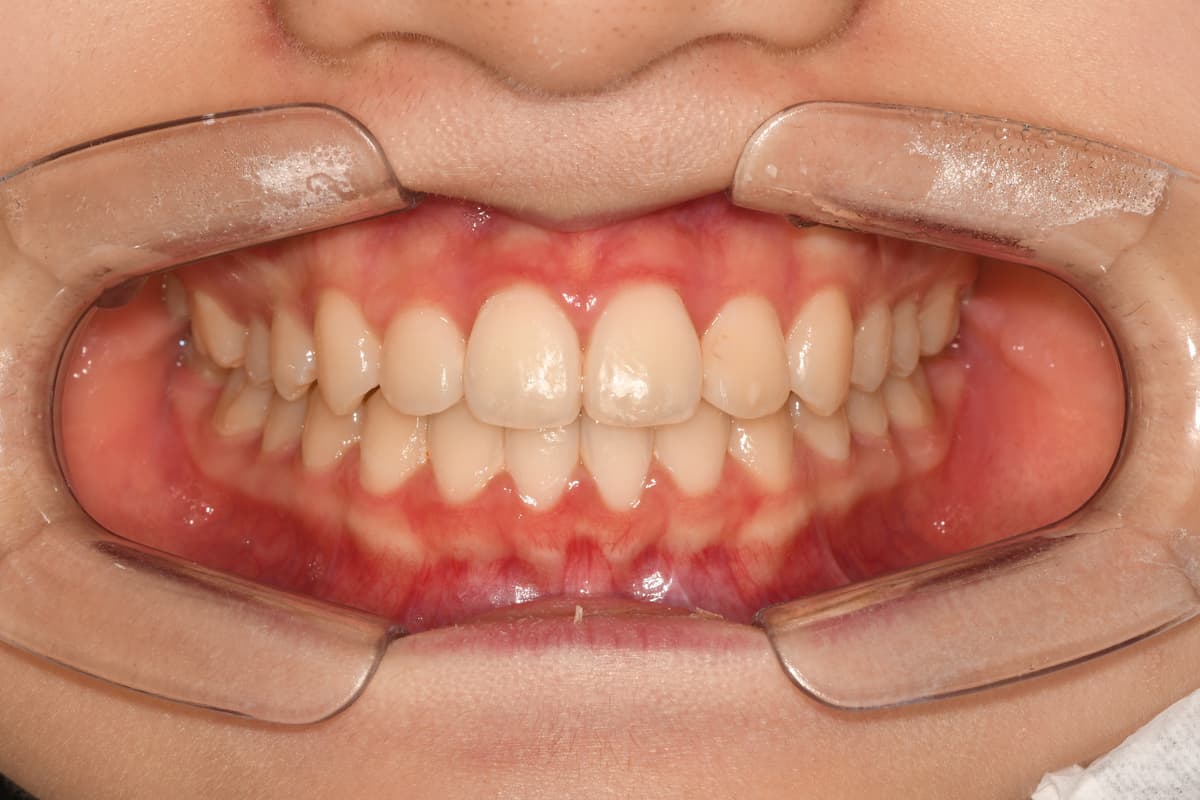

교정 치료 전후 사례

교정과 전문의가 직접 진료한

실제 환자 케이스입니다

이●● · 심한 부정교합